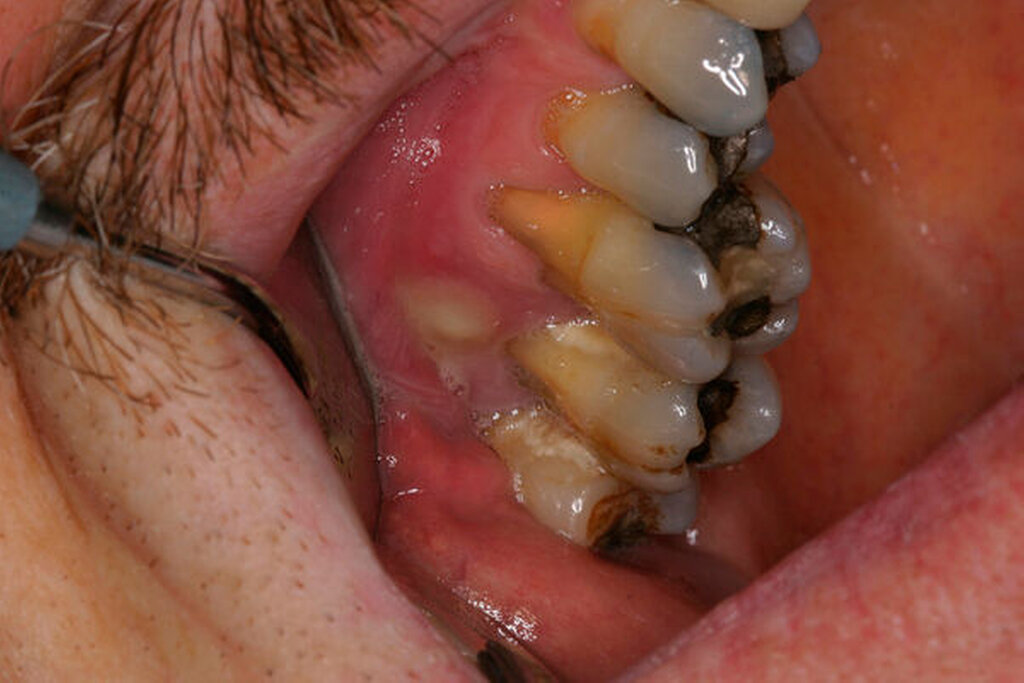

Ein 59-jähriger Patient stellte sich erstmals 2015 mit rezidivierenden pochenden Beschwerden und zeitweise zusätzlich auftretendem Pusaustritt an Zahn 16 vor. Klinisch zeigte sich ein ausgeprägter Attachmentverlust distal mit bis apikal sondierbarer distobukkaler Wurzel, Furkationsbeteiligung und Pusaustritt sowohl über den Parodontalspalt als auch durch einen distobukkal gelegenen Fistelausgang. Zunächst erfolgte die endodontische Behandlung des Zahnes 16 mit anschließender systematischer PA-Therapie. Bei persistierender parodontaler Problematik an 16 wurde die Möglichkeit der Teilamputation der distobukkalen Wurzel mit dem Patienten diskutiert, um die Hygienefähigkeit und damit die Prognose des Zahnes zu verbessern. Auch über die Extraktion als Alternative wurde der Patient aufgeklärt. Er war allerdings motiviert, seinen Zahn so lange wie möglich zu erhalten.

So erfolgte die Amputation der distobukkalen Wurzel mit anschließender Versorgung des Zahnes mittels Vollkrone. Die Situation an 16 ist seitdem für den Patienten subjektiv stabil, die aktuelle Röntgenkontrolle zeigt jedoch eine Progredienz der parodontalen Defekte trotz regelmäßiger UPT und subjektiv guter Mitarbeit des Patienten, was die Prognose des Zahnes negativ beeinflusst. Ursächlich hierfür kann eine persistierende parodontale Infektion durch den trotz Wurzelamputation immer noch schwer für die häusliche Mundhygiene zugänglichen Furkationsbereich mit enger Lagebeziehung der mesiobukkalen und der palatinalen Wurzel sein. Der Patient ist allerdings aktuell mit der Situation zufrieden und beschwerdefrei und wünscht daher noch keine Extraktion des Zahnes, auch wenn diese sich nun fünf Jahre nach dem initialen Befund nicht mehr sehr lange vermeiden lassen wird.

Ursachen für mögliche Misserfolge scheinen aus parodontaler Sicht vor allem Faktoren wie der Grad der Furkationsbeteiligung, ein bereits vorhandener Knochenabbau und Tabakkonsum zu sein [Dannewitz et al., 2006]. Allerdings scheinen Zähne, die aus parodontalen Gründen wurzelamputiert wurden, eine bessere Prognose zu haben als jene, bei denen die Amputation aufgrund von Frakturen oder kariösen Defekten erfolgte, wobei ein Knochenniveau von mindestens 50 Prozent an den verbleibenden Wurzeln einen positiven Einfluss auf die Prognose zu haben scheint [Park et al., 2009]. Alassadi et al. identifizierten bei einer Misserfolgsrate von 44,7 Prozent vor allem Frakturen, Karies und parodontale Defekte als Hauptgründe für Misserfolge amputierter Zähne [Alassadi et al., 2020]. Jedoch kann auch die Zahnanatomie nach der Amputation den Erfolg beeinflussen. Sind nach der Amputation subgingival Zahnanteile vorhanden, die nicht optimal geglättet sind [Newell, 1991], kann dies die Prognose verschlechtern. Auf die Beseitigung von mikrobiellen Retentionsnischen wie belassenen Überhängen und Rauigkeiten ist bei der chirurgischen Durchführung und später bei der prothetischen Versorgung daher zu achten.